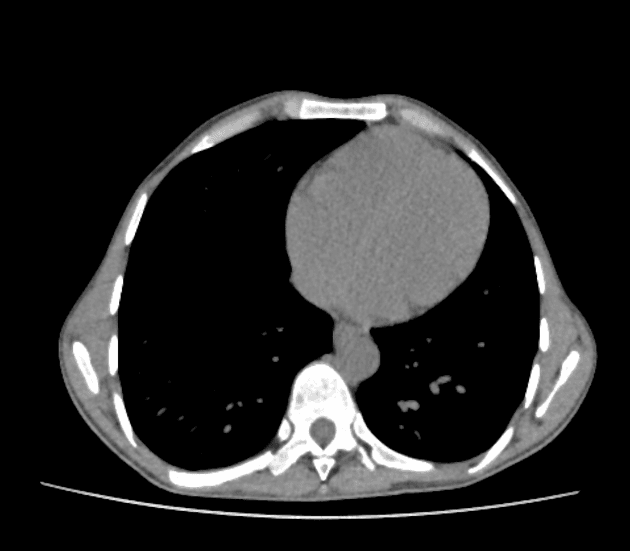

Axial C+ arterial phase

CT•Axial C+ arterial phase•1 / 427

- Khối ở thuỳ trên bên trái, vị trí trong trung thất, có vôi hóa một phần, tiếp giáp với màng phổi trung thất và động mạch dưới đòn trái, không có xâm lấn hoặc bao quanh mạch máu (no invasion or vascular encasement).

- Nốt mô mềm không vôi hóa liền kề (adjacent non-calcified soft tissue nodule).